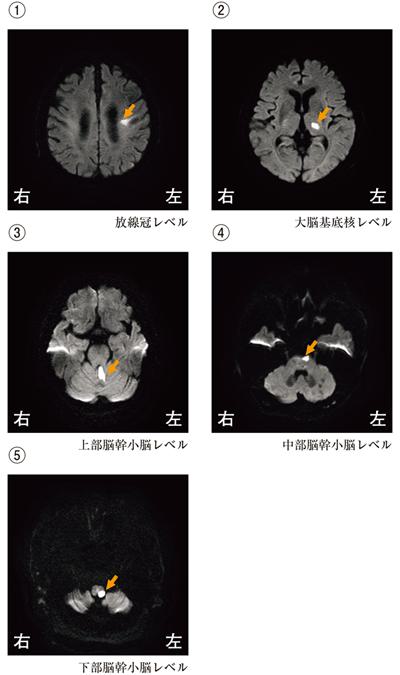

78歳の男性。脳梗塞。左顔面神経麻痺および右片麻痺を呈する。頭部MRIの拡散強調像を示す。梗塞巣として考えられるのはどれか。

1

①

2

②

3

③

4

④

5

⑤